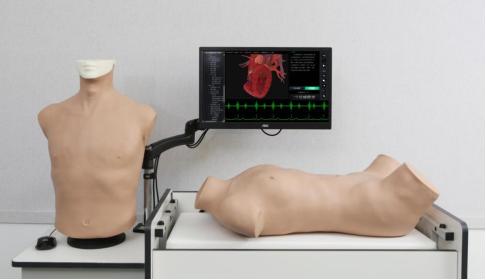

超声模拟实训系统 单机版(女)

超声模拟实训系统 单机版(女)

超声模拟实训系统 单机版(男)

超声模拟实训系统 单机版(男)

超声模拟实训系统 学生机

超声模拟实训系统 学生机

超声模拟实训系统 教师机

超声模拟实训系统 教师机